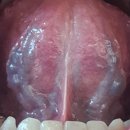

췌장암/혀//8맥교회혈/금진옥액/와사증/기적의 민간요법/중풍 2025.05.04해당카페글 미리보기

다민한의원 원장님께서 금진옥액 치료하세요. 설하사혈만 40 년간 전문으로 하시는 선생님이 계시는데요, 직접 하시지는 않고. 샾을 하시는 분에게는 직접 그 기법을 전수해 주십니다. 교육비는 극히 비싸고요. 이분이 몇몇 한의사들에게도 전수해주셨다고...